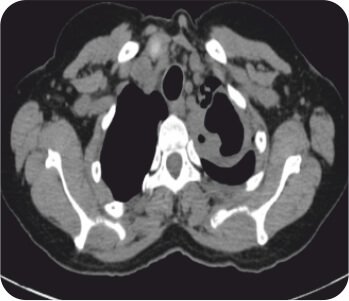

Pre procedure CT Scan

CT chest with thoracic angiogram revealed bilateral cavitary lesion with hypertrophied collateral arteries predominantly supplying the right upper lobe cavity. FOB done showed active bleeding from right upper lobe bronchus.